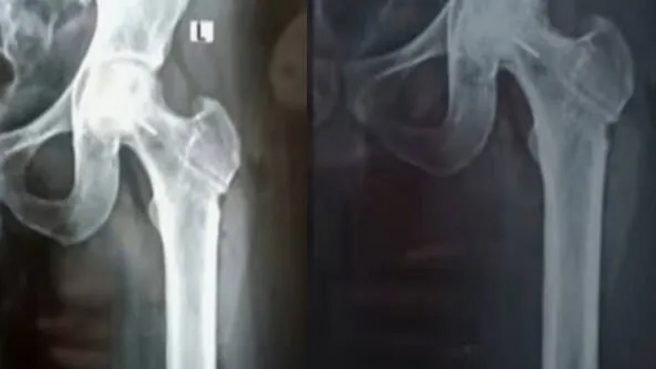

തിരുവനന്തപുരം ജൂബിലി മെമ്മോറിയൽ ആശുപത്രിക്കെതിരെ ഗുരുതര ചികിത്സാപിഴവ് പരാതി. ഇടുപ്പ് എല്ലിൽ ശസ്ത്രക്രിയ ചെയ്യുന്നതിനിടെയാണ് ചികിത്സ പിഴവുണ്ടായിരിക്കുന്നത്. രക്തയോട്ടം കൂട്ടാനുള്ള ശസ്ത്രക്രിയക്കിടെ ഡ്രിൽ ബിറ്റ് ഒടിഞ്ഞു കയറുകയായിരുന്നു. മലയിൻകീഴ് സ്വദേശി ജിജിൻ ജോസിൻെറ ഇടത് ഇടുപ്പ് എല്ലിലാണ് ഡ്രിൽ ബിറ്റ് ഒടിഞ്ഞു കയറിയത്. ജിജിൻെറ പരാതിയിൽ കൻോൺമെന്റ് പൊലീസ് കേസെടുത്തിട്ടുണ്ട്. ലോഹ കഷണം നീക്കം ചെയ്യാനാകില്ലെന്നും ലോഹ കഷണം ഇരിക്കുന്നതിനാൽ പ്രശ്നങ്ങളുണ്ടാകില്ലെന്നും രോഗിയെ അറിയിച്ചതാണെന്ന് ആശുപത്രി അധികൃതർ വ്യക്തമാക്കുന്നു.